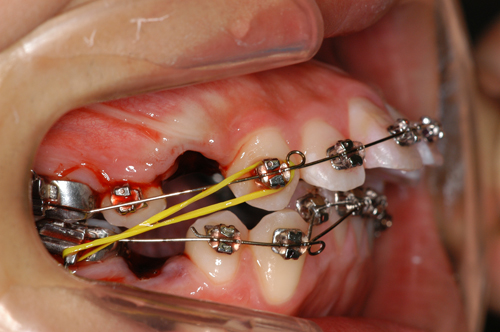

患者:14歳8ヶ月 男性

抜歯部位:上顎、第一小臼歯 下顎第二小臼歯

動的治療期間:18ヶ月